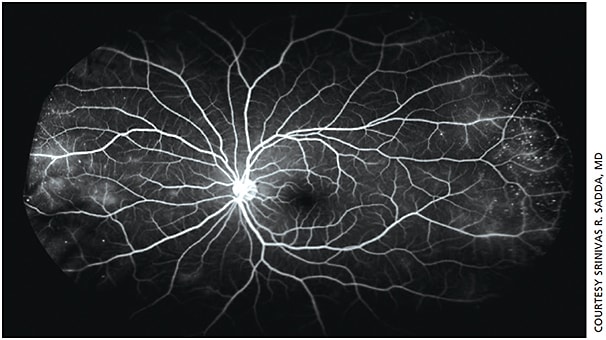

Now that we treat some proliferative diabetic retinopathy patients with anti-angiogenic therapies, identifying and following areas of neovascularization is of paramount importance (Figure 3). In addition, recognizing peripheral nonperfusion is increasingly important, as the amount of peripheral nonperfusion appears to predict the likelihood of neovascularization development and the extent of macular edema. Laser photocoagulation to these areas of nonperfusion is considered a potential treatment option, especially in patients who seem to be suboptimally responsive to pharmacotherapy. The value of this is still being characterized in ongoing clinical trials.

Figure 3. Widefield fluorescein angiogram of the left eye of a 57 y.o. Latino male with poorly controlled diabetes. Evidence of proliferative diabetic retinopathy with multiple small areas of neovascularization and peripheral nonperfusion (especially temporally) are evident.